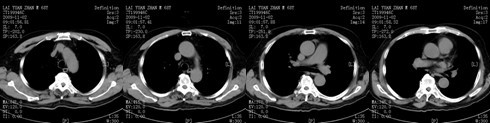

图5 肺血管增强扫描

(肺血管增强扫描见肺部无实变性信号影,连续血管造影增强扫描见肺动脉无充盈缺损)